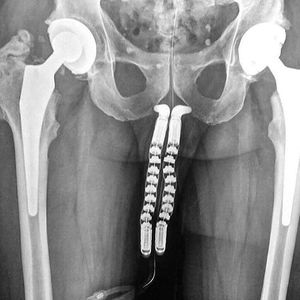

There are different kinds of penile implants used in phalloplasty. Phalloplasty is the construction or reconstruction of a penis. The phalloplasty is a common surgical choice for transgender and nonbinary people interested in gender confirmation surgery. It’s also used to reconstruct the penis in cases of trauma, cancer, or congenital defect. The goal of a phalloplasty is to build a cosmetically appealing penis of sufficient size that is capable of feeling sensations and releasing urine from a standing position. It’s a complex procedure that often involves more than one surgery. Follow us @medshots for more